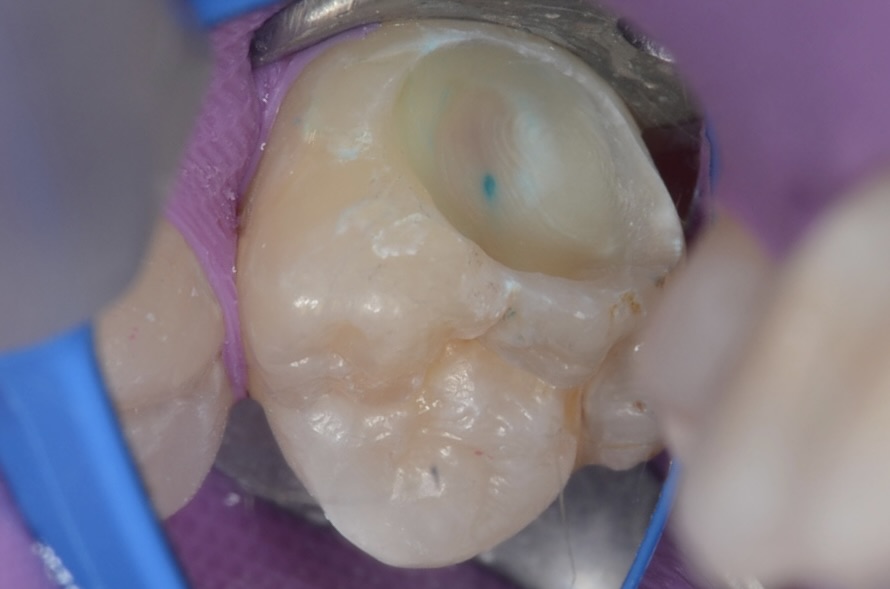

古いレジンを取り除き、齲蝕検知液で虫歯を染めました。 -

齲蝕検知液に染まる虫歯

広範囲に虫歯が青く染まっています。 -